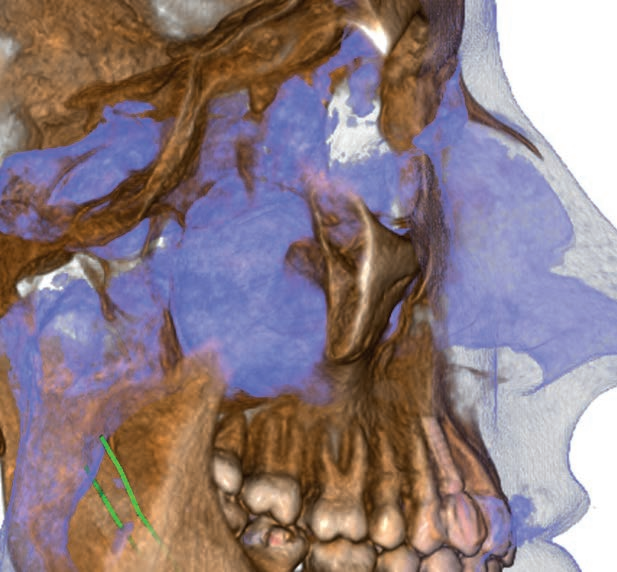

Hyperion X5全景、头颅和X射线体层摄影设备

Hyperion X5不断进化发展,现在头颅及3D拍摄也来到您的面前。这边在整个拍摄过程中快速易用,确保了高分辨率的3D和2D图像、低辐射时间以及实时诊断所需的快速数据处理,改善医患沟通。新的虚拟控制面板简化了拍摄流程,并引入了上颌窦容积检查和正交全景图像的新程序。由于3D传感器模块的自动伺服控制运动,较短的检查时间确保了连续的愉快体验。

完整3D:包含牙列和上颌窦范围